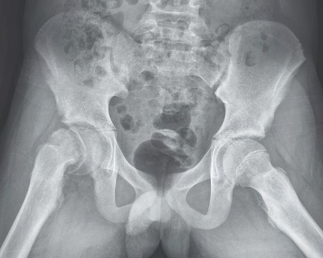

Recent studies indicate that Generative Pre-trained Transformer 4 with Vision (GPT-4V) outperforms human physicians in medical challenge tasks. However, these evaluations primarily focused on the accuracy of multi-choice questions alone. Our study extends the current scope by conducting a comprehensive analysis of GPT-4V's rationales of image comprehension, recall of medical knowledge, and step-by-step multimodal reasoning when solving New England Journal of Medicine (NEJM) Image Challenges - an imaging quiz designed to test the knowledge and diagnostic capabilities of medical professionals. Evaluation results confirmed that GPT-4V outperforms human physicians regarding multi-choice accuracy (88.0% vs. 77.0%, p=0.034). GPT-4V also performs well in cases where physicians incorrectly answer, with over 80% accuracy. However, we discovered that GPT-4V frequently presents flawed rationales in cases where it makes the correct final choices (27.3%), most prominent in image comprehension (21.6%). Regardless of GPT-4V's high accuracy in multi-choice questions, our findings emphasize the necessity for further in-depth evaluations of its rationales before integrating such models into clinical workflows.